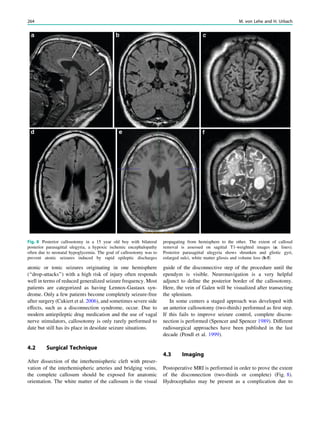

The Wada Test HorstUrbach and Jo¨rg Wellmer Contents 1 Introduction.......................................................................... 51 2 Angiographic Work-Up ...................................................... 52 2.1 IAP ......................................................................................... 52 2.2 Selective Wada Test.............................................................. 52 3 Complications Related to the Wada-Test......................... 53 4 Neuropsychological Work-Up ............................................ 53 5 Drugs ..................................................................................... 55 5.1 Amobarbital ........................................................................... 55 5.2 Methohexital .......................................................................... 55 5.3 Etomidate............................................................................... 55 5.4 Propofol.................................................................................. 55 References...................................................................................... 55 Abstract The Wada test or intracarotid amobarbital procedure (IAP) consists of the short inactivation of one brain hemisphere due to the injection of amobarbital or another short-acting anesthetic into the supplying inter- nal carotid artery (ICA). During the subsequent inacti- vation period, neurological functions such as language and memory can be tested to assess the respective functional reserve capacity of the contralateral hemi- sphere. Less frequent indications for a Wada test are the assessment of motor function and the identification of secondary bilateral synchrony in EEG. With the advent of high-resolution structural MRI assuring the morpho- logical integrity of the contralateral temporal lobe or hemisphere and functional MRI (fMRI) the number of Wada tests within the presurgical work up of epilepsy patients has decreased. However, it is still method of choice in epilepsy patients with suspected atypical or bilateral language representations according to fMRI, in patients with lesions interfering with the BOLD effect (e.g., cavernomas), and in children or intellectually challenged patients, in which fMRI cannot be used. 1 Introduction The neurologist Juhn Wada (Wada 1949, translation in Wada 1997) reported the effects of unilateral intracarotid injections of amobarbital on language in an article published in Japanese in 1949. While at the Montreal Neurologic Institute in the 1950s, Wada introduced his technique in the presurgical evaluation of epilepsy patients to determine language later- alization before surgery (Wada and Rasmussen 1960). Within a few years, it became evident that this technique could also be used to assess memory capacity in patients who were candidates for temporal lobectomy or amygdalohippocamp- ectomy. In this pre-imaging era, further indications were the lateralization of the seizure focus and the prediction of H. Urbach (&) Department of Neuroradiology, University Hospital Freiburg, Germany e-mail: horst.urbach@uniklinik-freiburg.de J. Wellmer Ruhr-Epileptology, Department of Neurology, University Hospital Knappschaftskrankenhaus, Bochum, Germany H. Urbach (ed.), MRI in Epilepsy, Medical Radiology. Diagnostic Imaging, DOI: 10.1007/174_2012_619, Ó Springer-Verlag Berlin Heidelberg 2013 51

• 56.

postoperative outcome (Spenceret al. 2000; Lee et al. 2003; Baxendale et al. 2008, Baxendale 2009 ). For more selective memory testing and in order to avoid confounding effects of hemispheric language inactivation, selective Wada tests with amobarbital injections into the posterior cerebral artery (PCA), the anterior choroidal artery (AchoA) or the middle cerebral artery or its branches have been developed (Jack et al. 1988, 1989; Wieser et al. 1997; Urbach et al. 2001, 2002). However, as an invasive procedure with an inherent risk of permanent neurological deficits, Wada tests are per- formed on selected patients only occasionally (Haag et al. 2008; Wagner et al. 2012). 2 Angiographic Work-Up 2.1 IAP A 5F sheath is placed in the femoral artery ipsilateral to the intended intracarotid injection side. A 5F vertebral catheter is navigated into both common carotid arteries and digital subtraction angiograms are obtained before the catheter is advanced into the ICA on the injection side. The reason for bilateral anterior circulation angiograms is to rule out prominent anastomotic channels from the ICA to the verte- brobasilar system and to assess the angiographic supply to the hemispheres (Fig. 1). For example, if both anterior cerebral arteries are fed via one ICA, amobarbital injection in this ICA often leads to an ‘‘mutistic’’ patient for the test period. Before amobarbital is injected via the placed catheter, the epileptological team starts the continuous EEG record- ing and may present initial memory material for later recall. In the Bonn protocol, the patient is then asked to elevate both arms and to count backwards from 100. While counting backwards, a 2 ml dose containing 200 mg amo- barbital in a 10 % solution is manually injected with a rate of approximately 1 ml/s (Kurthen et al. 1994; Wellmer et al. 2005). For alternative anesthetics, see below. During the injection period, the contralateral arm will fall and be gently caught captured by a third person. If the arm is hemiplegic and the EEG shows an ipsilateral slow- ing, hemispheric inactivation is likely and the catheter withdrawn, while the neurologist proceeds with the test. 2.2 Selective Wada Test A 6F guiding catheter is introduced through a 6F sheath and placed in the ICA the dominant vertebral artery. A 0.010 mi- crocatheter is navigated under fluoroscopic and ‘‘roadmap- ping’’ control in the P2-segment of the PCA (Figs. 2, 3), the origin of the AChoA, or the middle cerebral artery (Fig. 4). Fig. 1 IAP in a 28 year old woman with right-sided frontal lobe epilepsy and bilateral fMRI language representation. Bilateral ICA angiograms before a left-sided IAP show a more prominent right- than left-sided A1 segment of the anterior cerebral artery (ACA). With manual high pressure contrast injection into the right ICA, retrograde ACA and MCA opacification is obtained. However, with gentle and slow amoabarbital injections, each hemisphere is likely anaesthetized via the ipsilateral ICA 52 H. Urbach and J. Wellmer

• 57.